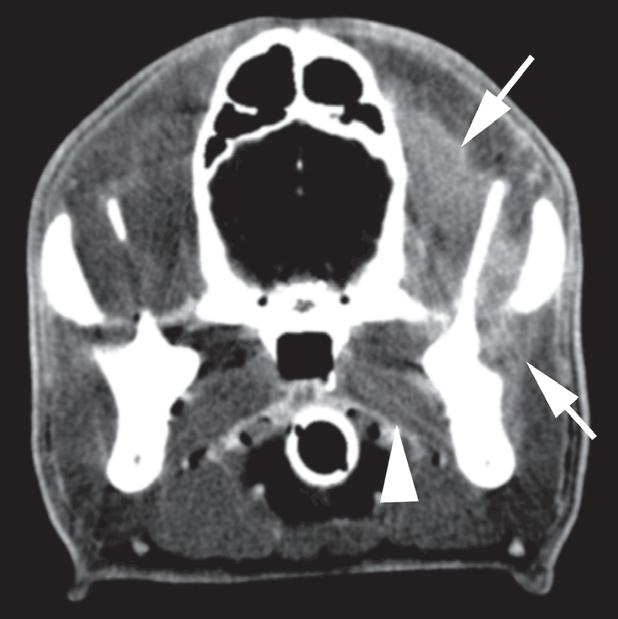

Badanie wykonano u 12-letniej, kastrowanej samicy labradora retrievera z wcześniej zdiagnozowanymi masami płucnymi i szyjnymi. W badaniu USG uwidoczniono kulisty, hipoechogeniczny guzek w obrębie prawego płata tarczycy (a). W TK masa jest nieznacznie hipodensyjna w obrazach bez wzmocnienia (b – strzałka). Lewy płat tarczycy ma prawidłową wielkość i jest hiperdensyjny (b – grot strzałki). Masa ulega umiarkowanemu wzmocnieniu po podaniu środka kontrastowego, jednak w mniejszym stopniu niż sąsiedni prawidłowy miąższ tarczycy (c – strzałka) i jej przeciwległy płat. W obrazach w rekonstrukcji grzbietowej w projekcji MIP po podaniu środka kontrastowego uwidoczniono przebieg obu tętnic szyjnych wspólnych dogrzbietowo względem płatów tarczycy (d – groty strzałek). Cieńszy przekrój MIP wykluczający tętnice szyjne ukazuje płaty tarczycy (e – strzałki) oraz lokalizację masy w obrębie prawego płata (e – grot strzałki). Biopsja wycinkowa wykazała raka tarczycy o utkaniu litym i pęcherzykowym z naciekaniem naczyń i torebki

Rycina 1.11.6. Rak tarczycy i gruczolak tarczycy (pies) TK

Badanie wykonano u 12-letniej, kastrowanej samicy owczarka australijskiego z prawostronną masą w dobrzusznej części szyi. Badanie USG wykazało dużą, litą, unaczynioną masę w obrębie prawego płata tarczycy (a) oraz mniejszą, hipoechogeniczną masę w obrębie lewego płata (b). Obrazy TK przed i po podaniu środka kontrastowego (c–f) ułożone od doczaszkowych do doogonowych ukazują dużą, prawostronną, jednorodnie wzmacniającą się masę (c–f – duża strzałka) z niewyraźną granicą dobrzuszną oraz pozatorebkowym szerzeniem się i rozlanym wzmocnieniem pokontrastowym przyległych tkanek (e, f – grot strzałki). W obrazie bardziej doczaszkowym widoczny jest prawidłowy lewy płat (c, e – mała strzałka), natomiast w obrazie bardziej doogonowym jest on powiększony i ma niższą gęstość, niż można by oczekiwać, co sugeruje obecność drugiej, mniejszej masy (d, f – mała strzałka). W obrazach reformowanych wzdłuż osi długiej widać dwa małe guzki w lewym płacie (h – małe strzałki). Wyniki obrazowe potwierdzono podczas zabiegu (i, j – strzałki). Biopsja wycinkowa wykazała prawostronnego raka tarczycy z naciekaniem pozatorebkowym oraz lewostronnego gruczolaka tarczycy